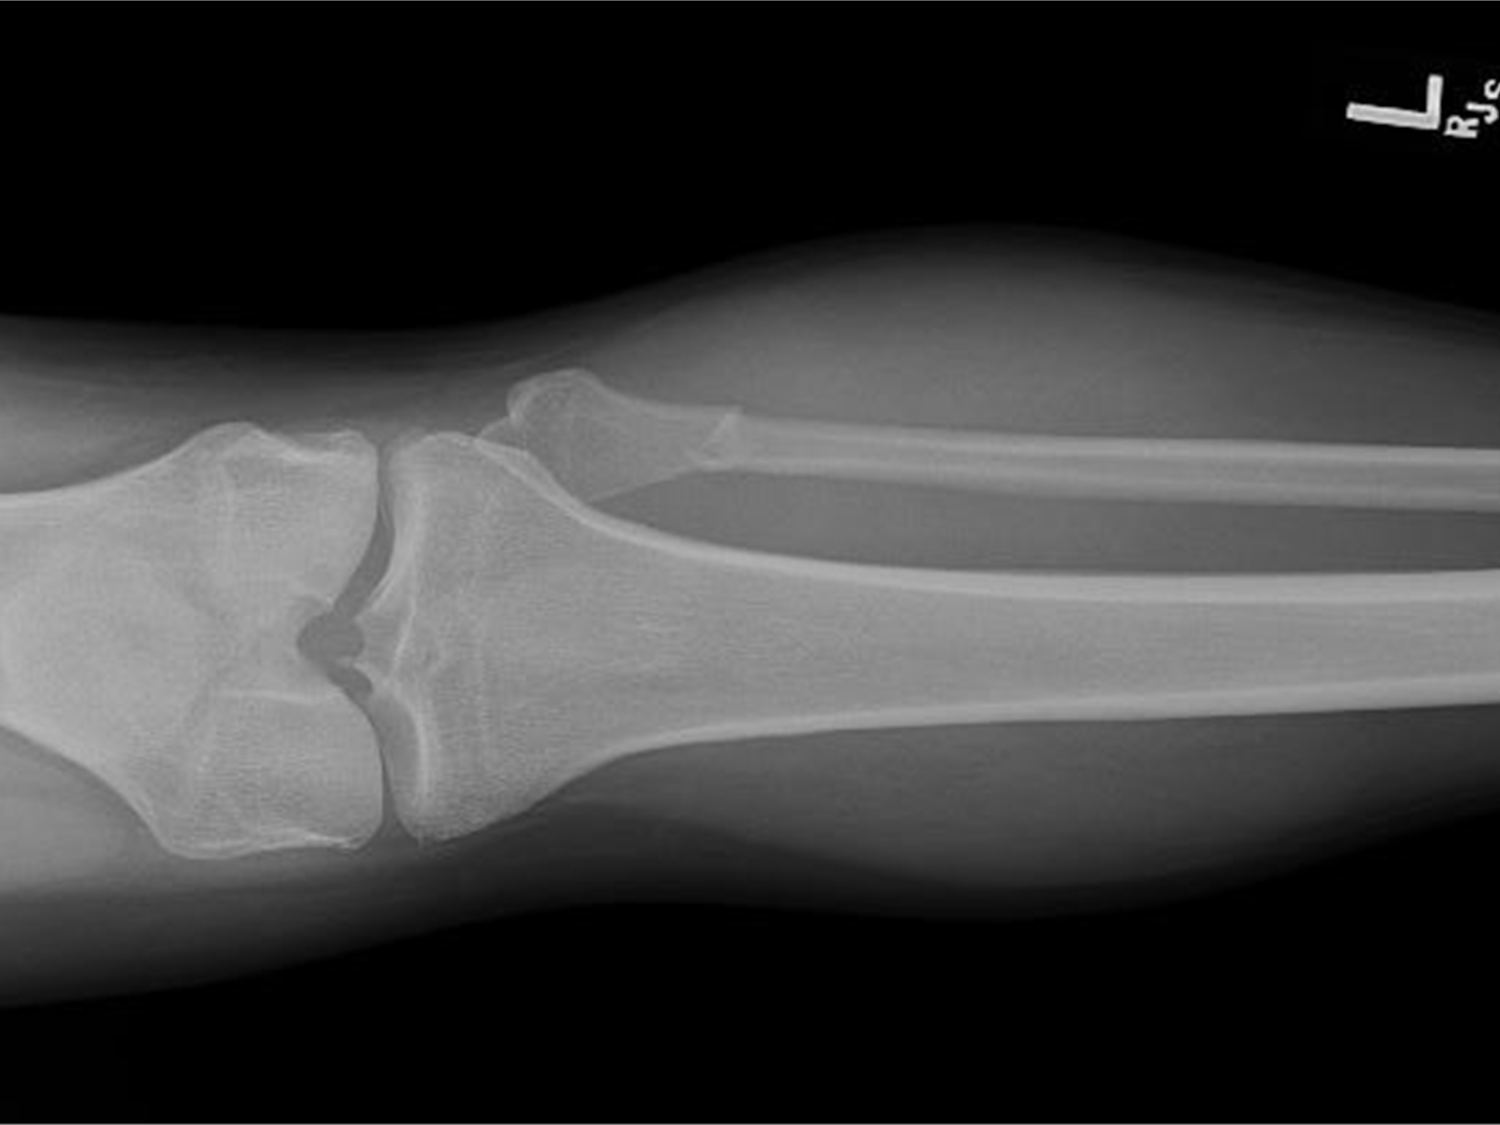

tibia

87

fibula

88

tibia (top) & fibula (bottom)